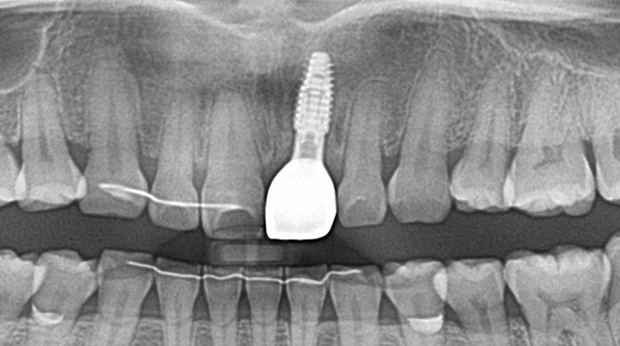

의식하진정법(수면마취)/임플란트